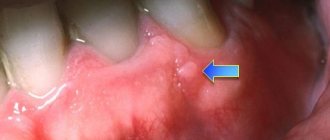

Figure 1. Actinomycosis of the maxillofacial region. Stage of fistula.